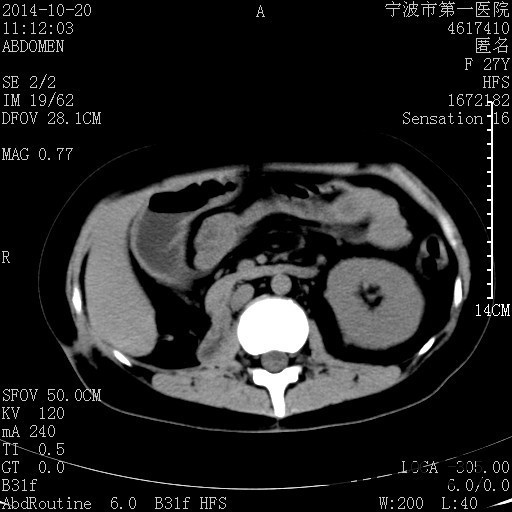

患者,女,27岁,因“右下腹疼痛伴呕吐2天”入院 患者无明显诱因出现右下腹疼痛伴呕吐、发热,体温最高39度,急诊CT示:右肾集气,考虑气性肾盂肾炎。

查体: 右肾区叩击痛,右下腹压痛,无反跳痛。 辅助检查: 空腹血糖9.7mmo/L,餐后血糖18mmol/L 血常规:白细胞 11.3*109/L, 中性百分比 77.4%, 血红蛋白 8g/L, 血小板 319*109/L 尿常规 WBC+++ 生化:白蛋白 37.5g/L,肝肾功能正常 泌尿系CT:右肾集气

诊断为“气性肾盂肾炎,感染性休克,糖尿病酮症酸中毒” 血、尿、脓液培养均示“克雷伯杆菌” 入院第2天行“右双J管置入术” 入院第3天、7天行“右肾穿刺造瘘术” 入院1月行“右肾切除术” 术后顺利康复出院。